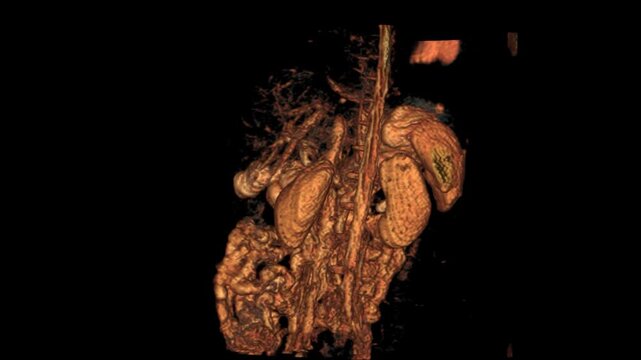

Comprehensive CT Abdomen coronal average VR movie displaying internal organ structures in high clarity. This 3D medical visualization captures detailed anatomy of the abdominal

00:15

CT Abdomen - movie in coronal plane with internal organs

00:10